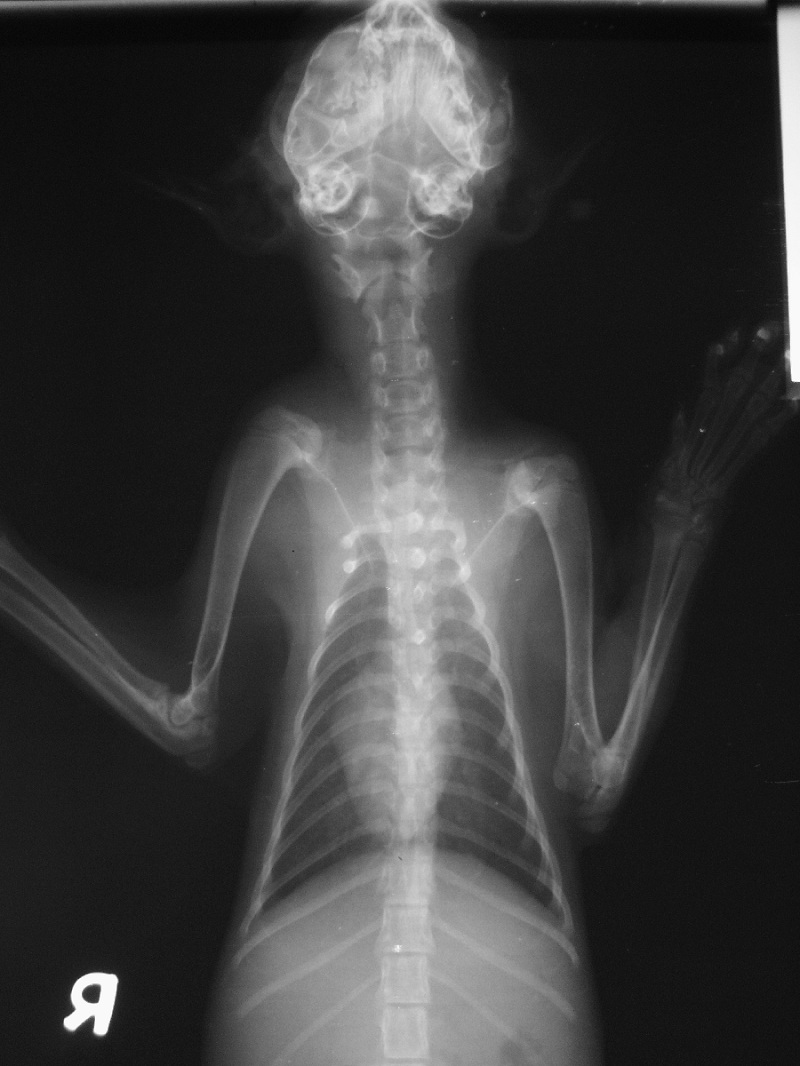

主題: 被車撞的貓 申請者姓名: WanLin Lu 花色: 申請日期: 2014-04-22 14:55:32 申請者部落格: 申請者臉書網址: 所在縣市/合作醫院: 高雄市/樂生動物醫院 治療費用: 6200元 需求人數: 8人 已結案 (2014-05-18 09:43:34) 報名人員: Patrick x2(已付款)、黃翠娥 x2(已付款)、cello x2(已付款)、Patrick Liu(已付款)、吳宜玲(已付款)、 候補人員: 動物病情說明: 我在6日晚上八點多時,正騎在高雄民族路機車道上,

忽然看到路中間有隻小貓躺在那,就騎回頭去看看,

發現牠還有呼吸,鼻子都是血,

就趕快把牠抓起來送往就近的樂生醫院,

醫生先做了止血跟消炎,

牠被撞的部位初步看都在頭部,

經詳細檢查後

小貓鼻腔流血且瞳孔大小不一,

第三眼臉脫垂 ,有腦神經受傷的現象,

血檢結果有貧血及肝指數高的現象,應該是撞擊引起的出血及肝臟傷害,日後會視恢復狀況再驗血追蹤指數。

貓咪4/10做了血檢雖肝指數仍有上升但發炎狀況已有改善且出血狀況已回穩,紅血球有上升的趨勢,

4/11照了X光片,所幸骨頭無重大傷勢

4/17肝指數降至正常

4/6-4/13這段期間一直點滴注射含降腦壓藥物

4/19出院,並由認養人直接接回動物近況說明: 貓咪在新主人的細心照顧下,環境適應良好,食慾不錯,是個活潑好動又很會搗蛋的小女孩,

之後也會一直持續追蹤。